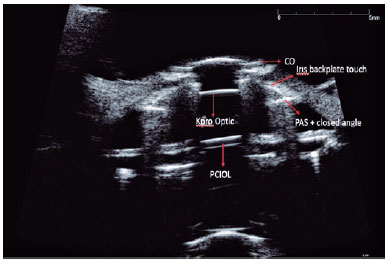

The UBM of all the patients was performed by the same experienced ophthalmologist. The patients were placed in the supine position. Topical anesthesia (0.5% proparacaine HCl) was applied to the eye for imaging, and an eye speculum was inserted. The device’s probe was placed in a transparent sheath filled with 5 ml of 0.9% saline and placed on the corneal surface for imaging. Images were acquired radially and horizontally at the central cornea and subsequently, through 360 degrees perpendicular and horizontal to the limbus. The anterior chamber structures, iridocorneal angle, ciliary processes, presence of RPM, current status of intraocular lens (IOL), and Ahmed glaucoma valve (AGV) tube status were assessed and recorded.

The anterior and posterior plates were viewed using UBM in 14 cases (Figure 2). RPMs were observed in three eyes (15%), and IOL haptics were viewed in three eyes. Significant angle narrowing was observed in four (57.1%) of the seven eyes without an AGV. However, three (23%) of the 13 eyes with an AGV demonstrated angle narrowing and iridocorneal adhesions. The tube tip was visualized in four patients (30.7%) who underwent AGV implantation with UBM (Table 1).

UBM has been an important tool in the diagnosis, evaluation, and follow-up of patients with glaucoma since it was first described as an imaging method with clinical importance in 1992 by Pavlin and Foster(21). Our study shows that UBM can also be an important tool for follow-up evaluation after keratoprosthesis as it can detect angle narrowing, RPMs, and IOL haptics. To the best of our knowledge, there is no study that reports the results of UBM for the follow-up of patients after keratoprosthesis.